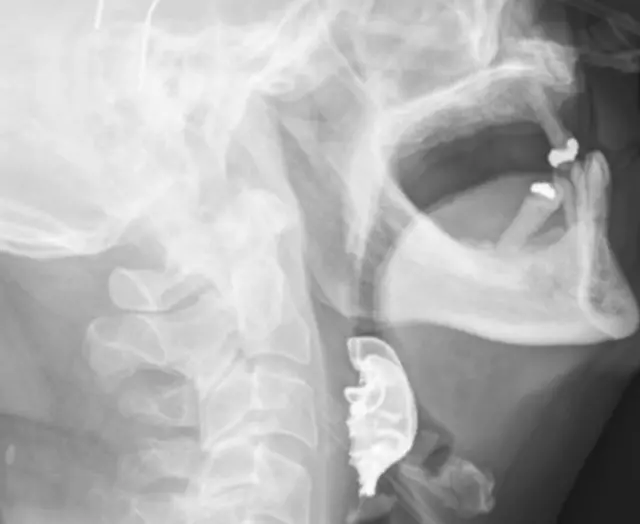

जब शल्यक्रियाको एक हप्तापछि बिरामीको घाँटीमा नक्कली दाँत भेटियो

ब्रिटेनमा एक वृद्ध व्यक्तिको नक्कली दाँत नियमित शल्यक्रियाका क्रममा घाँटीमा अड्किएको र आठ दिनसम्म फेला नपरेको तथ्य बाहिर आएको छ।

दुई दिनपछि ती व्यक्ति पुन: समस्या लिएर आएपछि चिकित्सकहरूले उनको घाँटीको जाँच गरेका थिए र त्यहाँ एउटा अर्धगोलाकार आकारको वस्तु अड्किएको फेला पारेका थिए।

त्यसपछि उनले चिकित्सकहरूलाई शल्यक्रियाका लागि अस्पतालमा समय बिताउँदा आफ्नो तीनवटा नक्कली दाँत हराएको बताएका थिए।